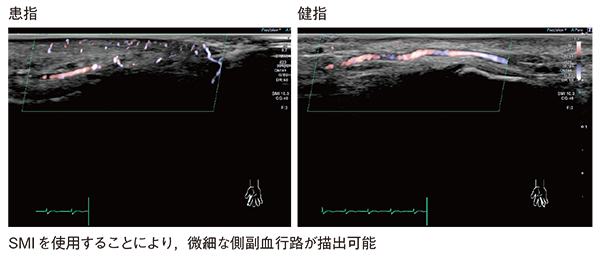

症例4は,レイノー現象の評価である。レイノー現象は,寒冷暴露やストレスにより血管攣縮が誘発され,左右対称性に両手指を侵すが,壊死や壊疽は認めない。エコー所見としては,血流の途絶や側副血行路の発達,cork screw signなどがみられる。本症例を24MHzリニアプローブとSMIを組み合わせて観察すると,患指では血流の途絶や微細な側副血行路が明瞭に描出された(図8)。

図8 症例4:24MHzリニアプローブとSMIによるレイノー現象の評価